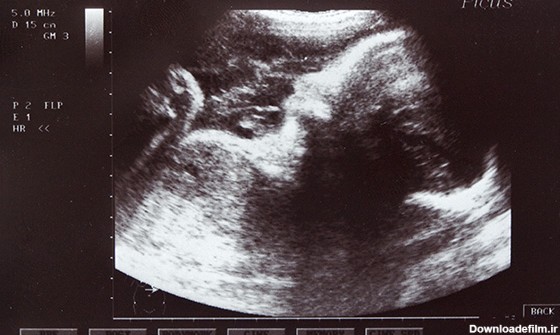

عکس جنین هفت ماهه دختر

در هفته هفتم بارداری تغییرات مهمی در بدن مادر اتفاق میافتد. ممکن است این تغییرات در ظاهر وی مشخص نباشد، ولی پایههای رشد و نمو جنین در ماههای آینده است.